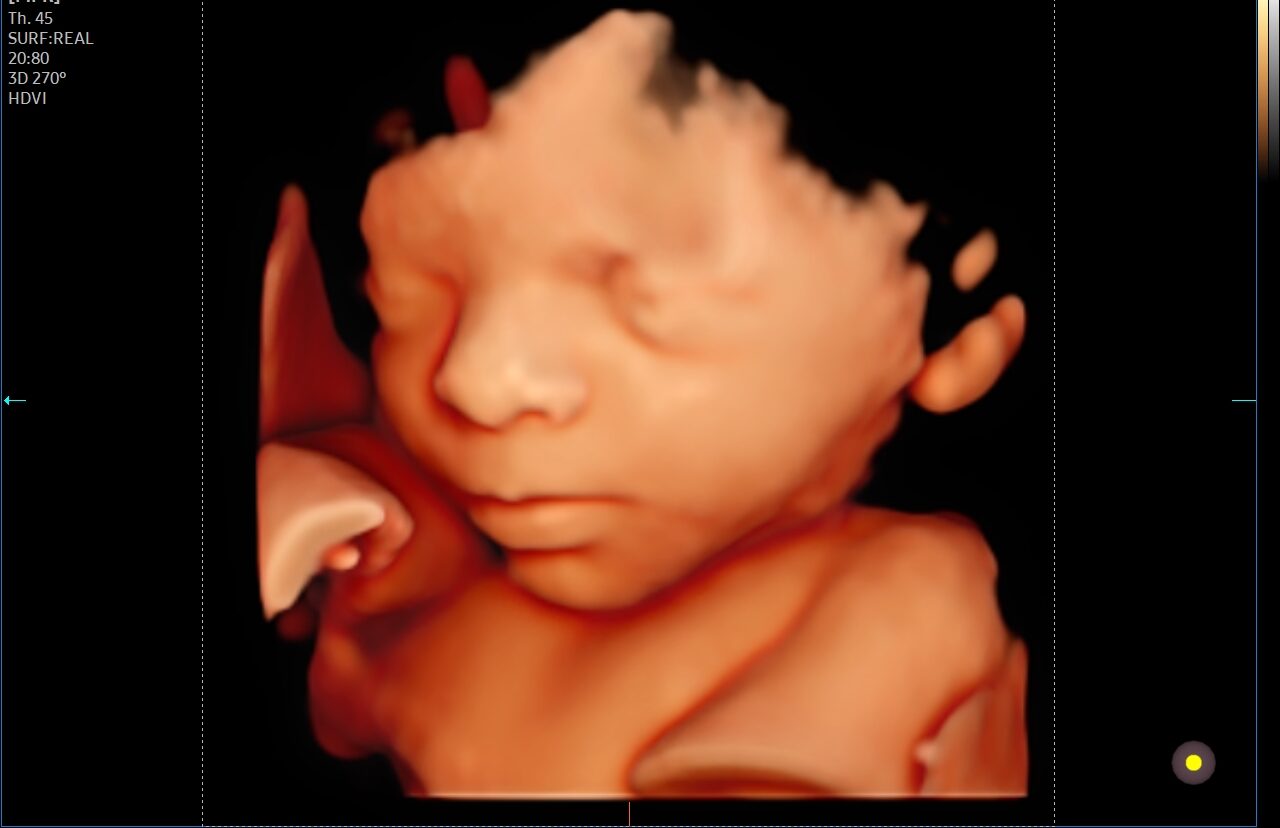

Pretecho’s

Professionele pretecho's om je baby haarscherp in 2D, 3D of 4D te bewonderen of het geslacht te weten te komen.